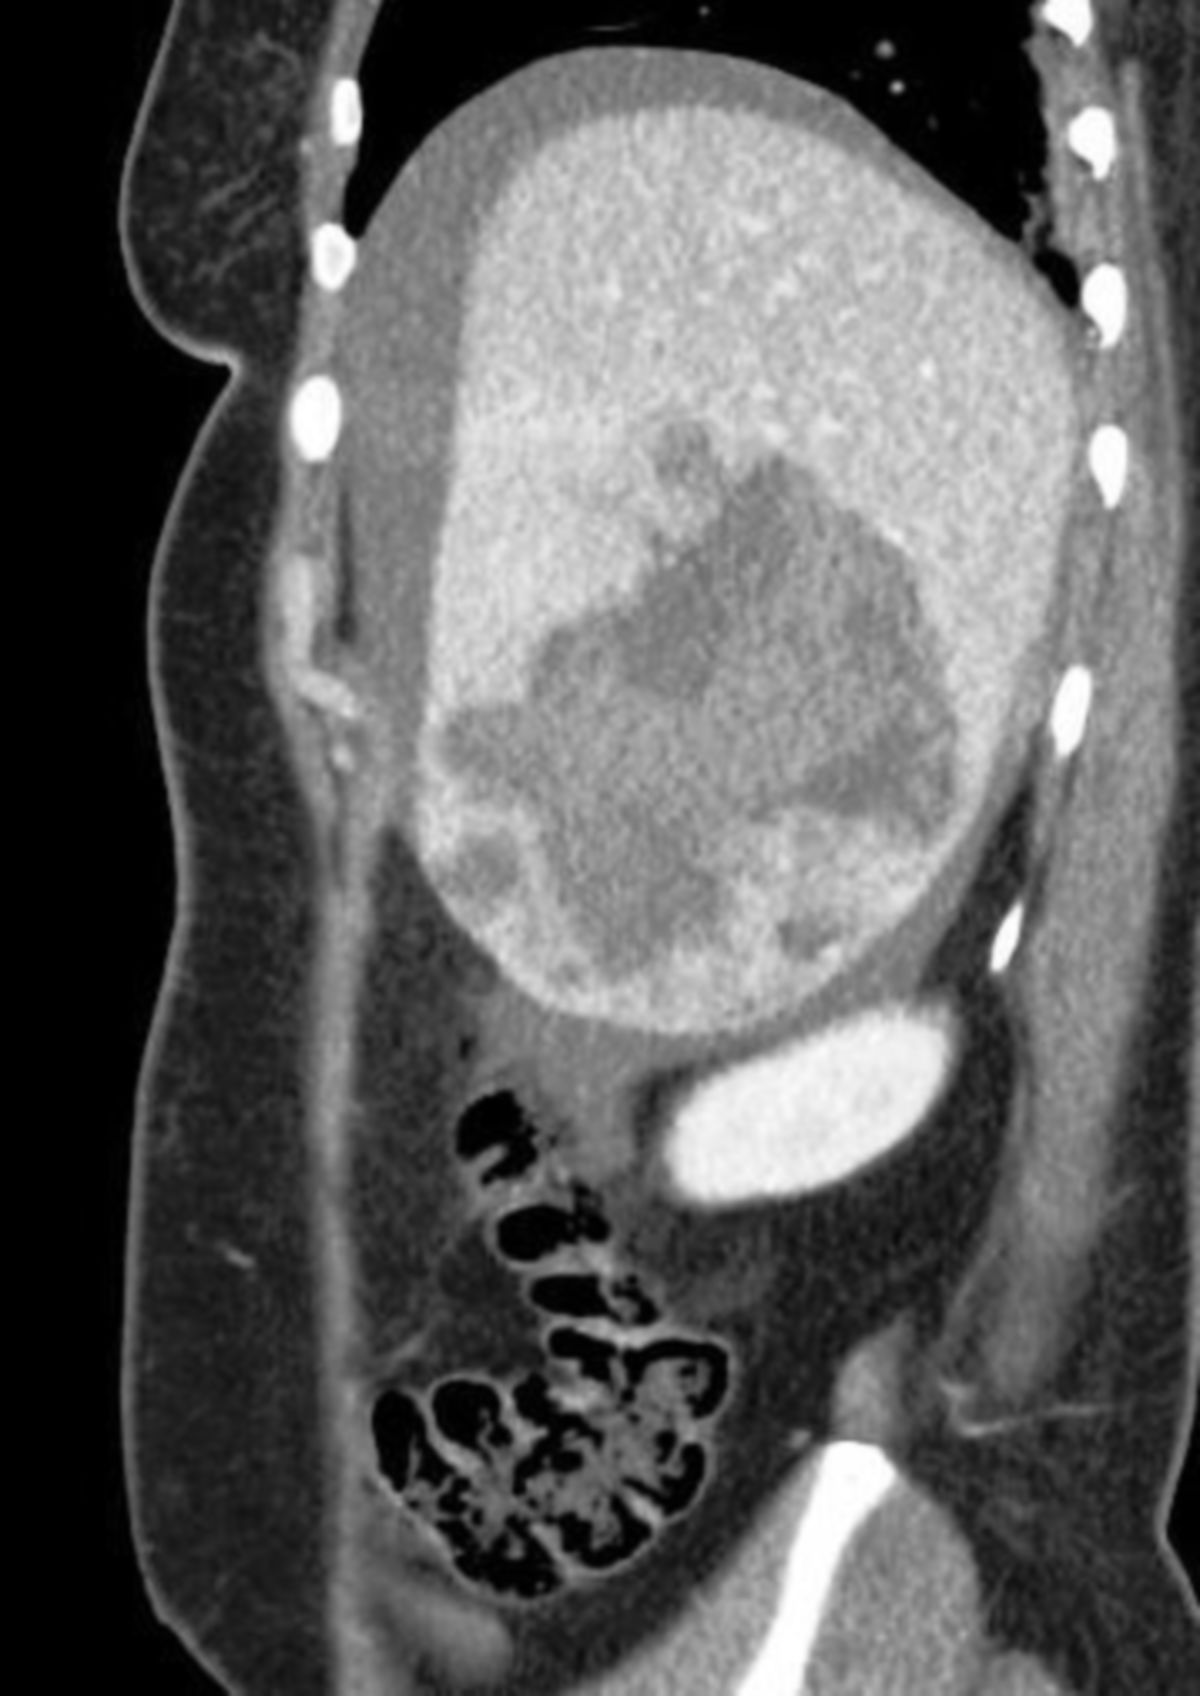

Pat mit Prellmarken im Gesicht und Hämatom im rechten Oberbauch, Schmerzen ausstrahlend in rechte Schulter.

NA nachfordern, Pat reagiert auf Ansprache, blass, CRT = 2, AW frei, O2-Gabe!, VAG bds, SpO2 97, HF 109, Sinustachyk., Zugang (!), bei Verschlechterung CRT > 2, Abwehrspannung Bauch, Hämatom re. OB, BZ 112, isokor, GCS 15, leichte Hämatome Kopf/Thorax, keine VE, NRS 8